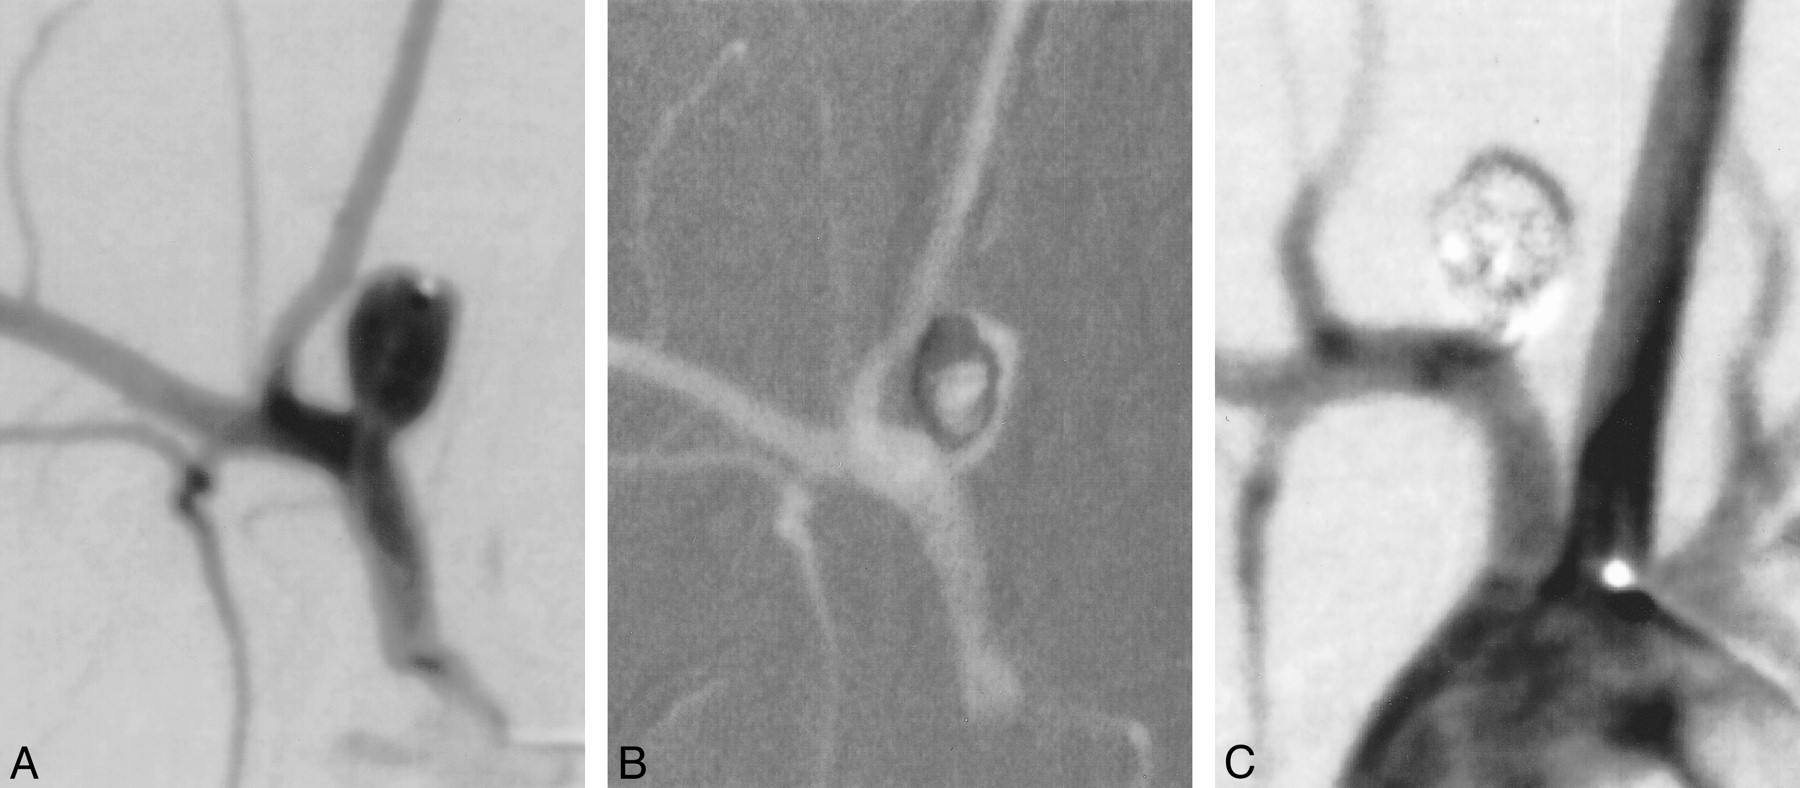

Right common femoral artery access in the rabbits was achieved as described previously herein. A 4F catheter was advanced into the ascending aorta. Using coaxial technique, with a continuous heparinized saline flush, a Tracker-10 2-marker microcatheter (Target Therapeutics, Freemont, CA) was advanced into the aneurysm (Fig 2). The size of the aneurysm was assessed using direct comparison to radiopaque sizing devices. The aneurysms were embolized with either a control (unmodified) or treatment (cell-bearing) coil. Previous investigations in our laboratory have determined that electrolysis has a deleterious effect on cell growth (unpublished data). Thus, the fibroblast-coated GDCs were deployed using a coil pusher device rather than the standard electrolytic detachment typically used for GDC coils. After coil embolization, the catheters were removed. The vascular sheath was removed, and the proximal aspect of the femoral artery was ligated with a 4–0 silk suture. The skin was closed with a running suture. Animals were allowed to recover and were sacrificed at 3 days (control [n = 3], treatment [n = 3]) 7 days (control [n = 3], treatment [n = 3]), and 2 weeks (control[n = 3], treatment [n = 3]) after embolization.

A, Experimental aneurysm accessed with microcatheter.

B, Coils deployed under roadmap fluoroscopy.

C, Control angiogram shows complete occlusion of the aneurysm.